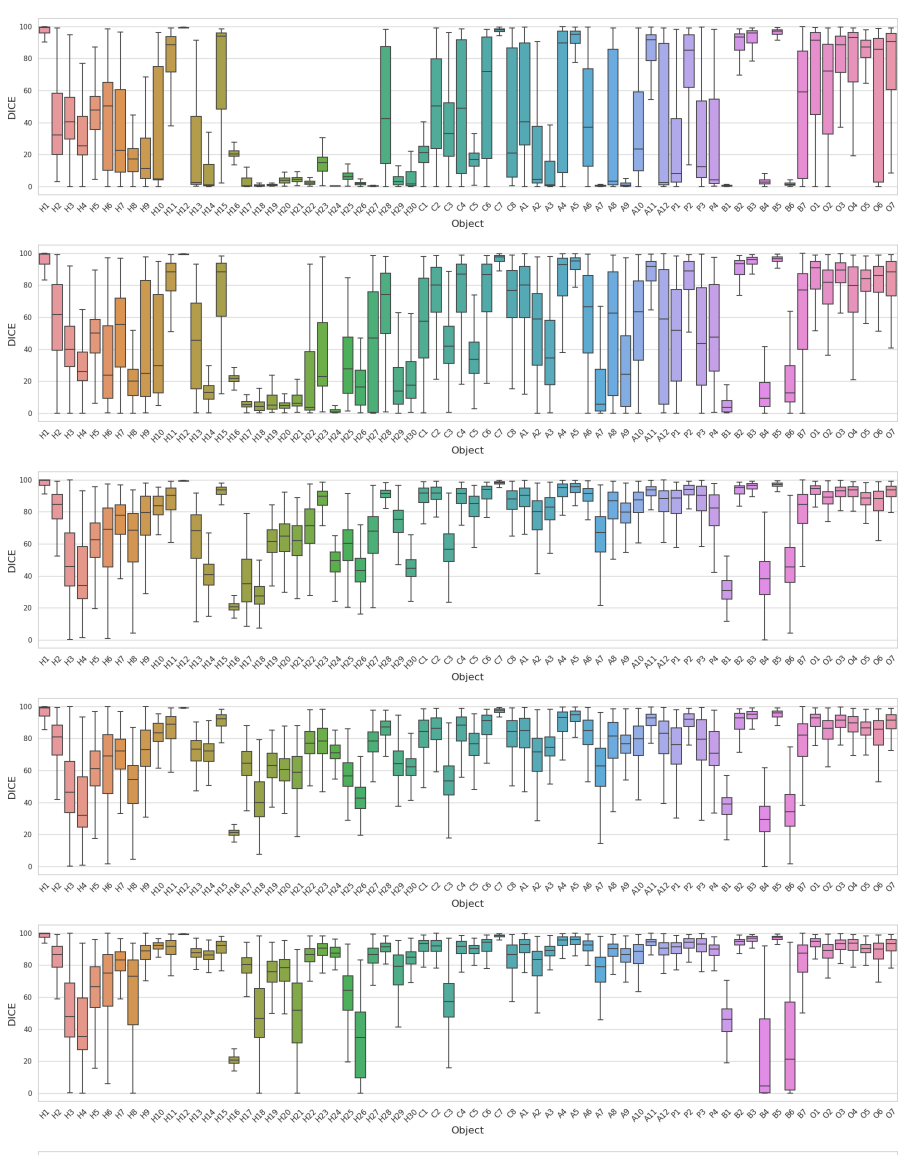

本研究全面地评估了SAM的各种模式在大规模、多样化的医学影像数据集上的分割性能,DICE指标评估结果如图4所示。

图4 不同测试策略的DICE箱线图。从上到下:S1H、S2、S3、S4、S5、S6。

基于实验分析,我们的主要结论如下:

- Everything模式不适用于大多数医学影像分割任务。在这种模式下,SAM对医学分割目标的感知能力较差,会输出大量的假阳性预测掩膜(图5)。

- 在Prompt模式下,加入更多前景点可显著提高SAM的分割结果。但医学影像中的前景和背景很容易混淆,随机加入负样本点可能会引起分割性能下降。此外,方框提示(S5)包含丰富的物体位置信息。因此,在我们的研究中,方框提示在大多数医学分割任务中比点提示表现好。在目前的研究中,混合策略(同时加入点提示和方框提示)的性能没有明显提升。这可能与SAM对混合提示的编码能力有关。图7和图8展示了SAM在各种测试策略下的可视化结果。

- 分割目标的不同属性可能影响SAM对医学分割目标的感知能力。特别是,SAM可能会对具有复杂形状、小面积或低对比度的目标分割效果不好。图9展示了DICE与目标的不同属性之间的关系。